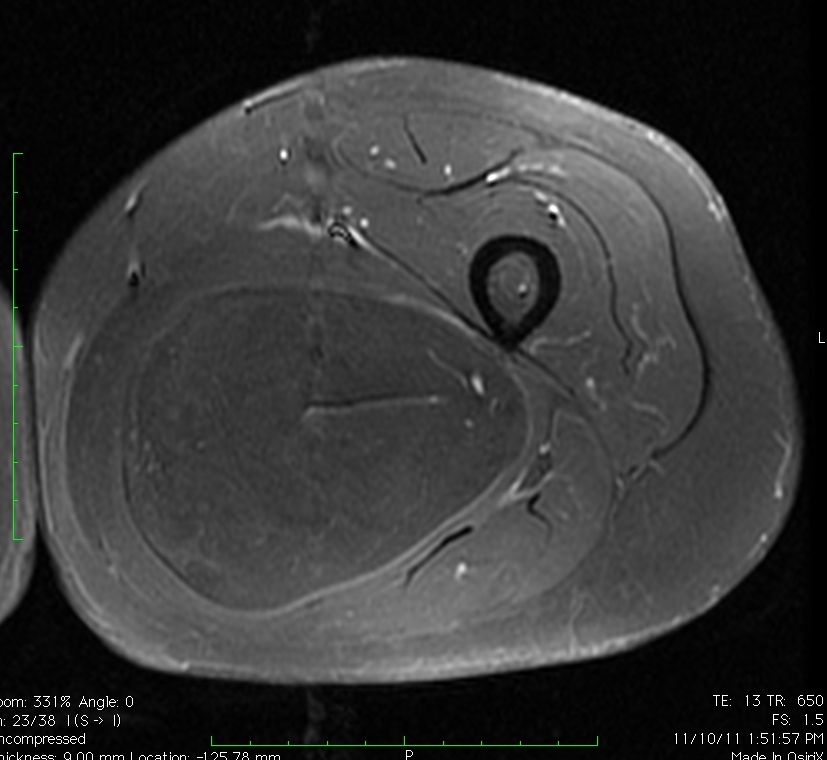

MRI

• Follows the signal characteristics of subcutaneous fat on all sequences

• T1: High Signal

• T2: Intermediate Signal; Low Signal with Fat Suppression

• Minimal or No enhancement with gadolinium

Fig. 1A, 1B, 1C, 2A, 2B, 2C: MRI of a lipoma: T1- weighted images shows an homogeneous mass in the posterior compartment of the thigh with high signal, saturates on fat saturated sequences with no or minimal enhancement. On T2-weighted images demonstrate an intermediate signal on FSE T2, saturates (becomes dark) on fat saturated sequences.